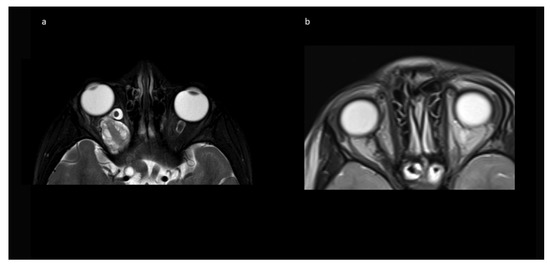

Indications for surgery were blindness/non-serviceable vision of the affected eye, disfiguring exophthalmos, pain, and documented tumor growth. A combination of factors was often present. All preoperative MRIs showed contrast-enhancing tumor growth from the orbit into the optic canal, and in 8/10, further intradural tumor extension affecting the ipsilateral optic nerve but not the optic chiasm (Figure 1).

No intraoperative or immediate post-operative complications were observed, and patients were usually discharged with orbital swelling and not yet or returning levator palpebra function. In the follow-up, two children developed enophthalmos, one with minimal levels and one with moderate ptosis due to levator palpebra muscle weakness. Both children had received radiotherapy prior to surgery. The other eight (80%) children had no obvious oculomotor or cosmetic deficit of eye position and movement. Figure 4 shows an example of resolution of exophthalmos on MRI after tumor removal.

3.6. Follow-Up

The mean follow up was 42.0 (range 2–74) months in Group A, and 15 months in Group B. Patients received MRIs at 3 months post-surgery, then in cases of no residual tumor, every 6 to 12 months, depending on previous tumor growth velocity for up to 5 years. The case with unintended STR (No 1, Table 1) showed tumor progression in imaging and was subsequently treated with chemotherapy. No further growth was observed thereafter. In the two cases from Group B, there was stability of the intended residual optic nerve within the optic canal and no signs of tumor recurrence originating from there. In two of the four cases with NF1, a very small contralateral optic nerve glioma (MRI signal intensity changes and minimal contrast uptake, but no significant tumor extension) was known prior to surgery. Since in both children, no impairment of vision (visus 0.8 and 1.0) existed, this tumor manifestation was only observed in accordance with guidelines that asymptomatic tumors do not deserve treatment. An exemplary MR image set is provided in Figure 7.

Figure 1. Exemplary MR-imaging of a 3-year-old male (a) preoperatively, (b) 1 month postoperatively, and (c) 2 years postoperatively.

Figure 4. Exemplary MR imaging follow-up of a child with (a) preoperative exophthalmos on the left side and (b) postoperative normal eye position.